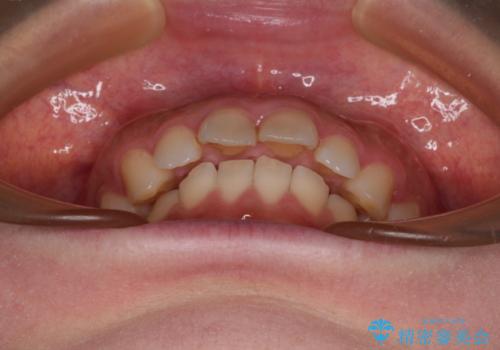

- 上の前歯が出っ歯と突出した口元を気にして来院された患者様です。

上顎歯列全体が前方に飛び出している印象であったので、上顎左右の第一小臼歯2本を抜歯し、ワイヤー装置にて抜歯矯正を行うこととしました。